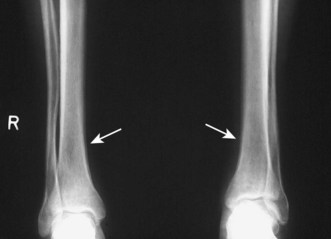

The standard chest X-ray is a posteroanterior (PA) view taken with the film in front of the anterior chest and the X-ray source 2 metres behind the patient (Fig. 7.22). In an anteroposterior (AP) film the X-ray source is in front of the patient, which tends to enlarge anterior structures such as the heart. Always compare an abnormal chest X-ray with previous films to see if abnormalities are resolving or longstanding.